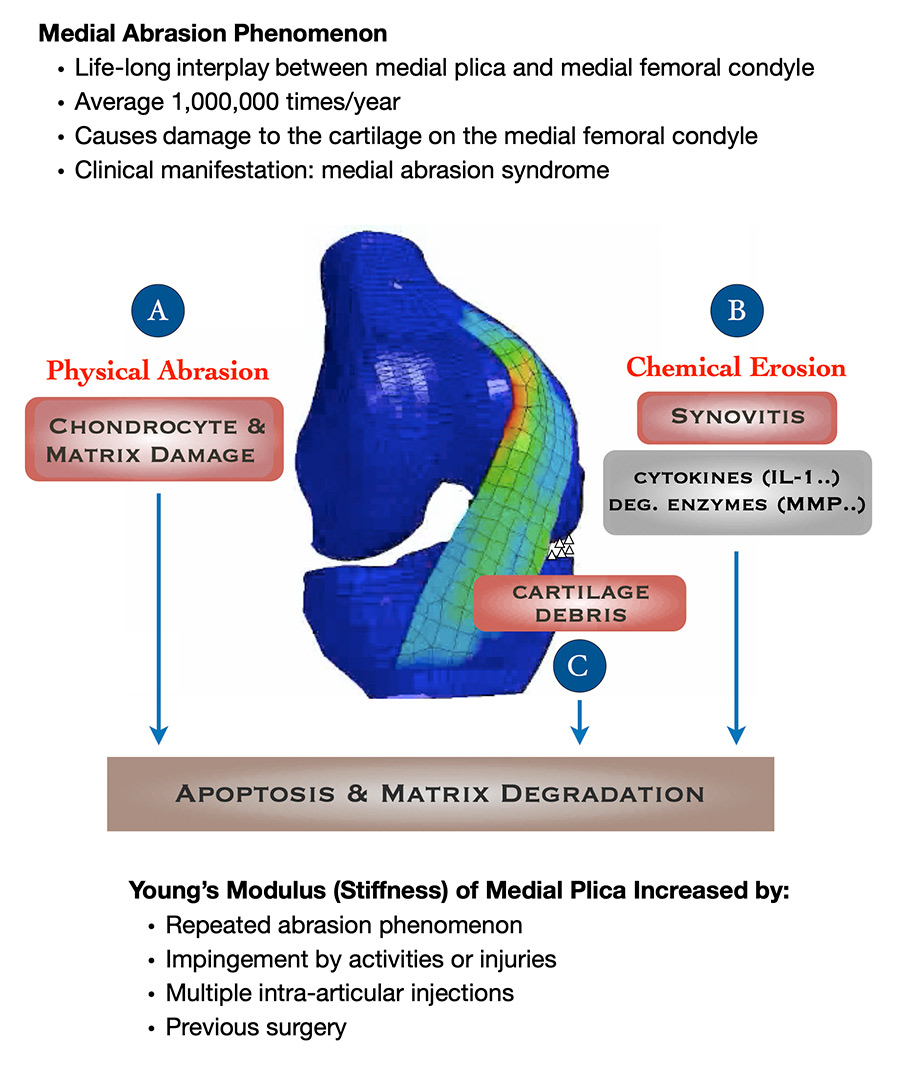

According to our series of studies, (1) the MAP can cause physical abrasion, which leads to cartilage debris and chemical erosions in the knee; all these factors then compound one another, making knee OA worse all the while. For example, more abrasion produces more cartilage debris which leads to more physical abrasion and synovitis (synovial inflammation); synovitis leads to biochemical erosion that further damages cartilage. A vicious circle ensues, and the patient suffers from worsening knee OA (Fig.1).